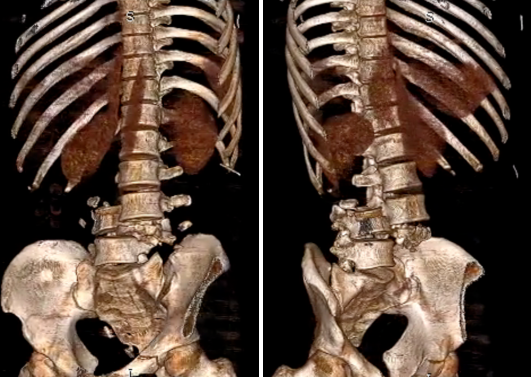

CT重建见第3和第4腰椎脱位

随后,患者直接被送入重症监护室。邵逸夫医院骨科赵凤东教授及其团队医生初步诊断,除车祸常见外伤外,患者还有一个最棘手的问题:腰椎的骨折脱位(L3-L4)及其继发的马尾神经损伤,患者双下肢感觉及活动均严重受损,大小便失禁。